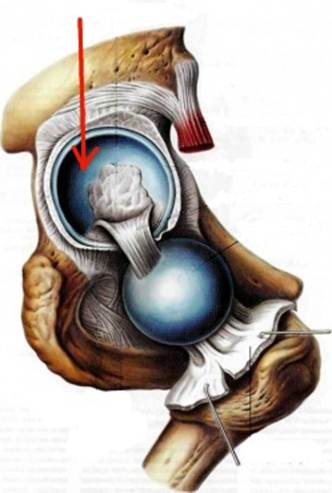

S: На рисунке обозначен art. Coxae (латинский язык).

S: Стрелка указывает на zona orbicularis

S: Стрелка указывает на lig. Ischiofemorale

S: Стрелки указывают на lig. iliofemorale

S: Стрелка указывает на lig. pubofemorale

S: Стрелка указывает на labrum acetabuli

S: Стрелка указывает на lig. Capitis femoris

S: Стрелка указывает на facies lunata